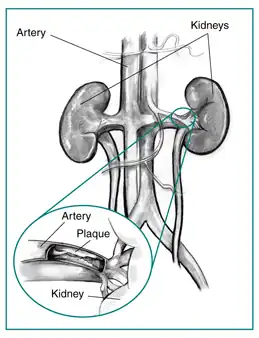

| Diagram of renal artery stenosis | |

Renal artery stenosis (RAS) is the narrowing of one or both of the arteries to the kidneys.[3] Early on there are typically no symptoms, while later high blood pressure or kidney problems may occur.[3] The blood pressure may be difficult to treat.[2] Complications may include chronic kidney disease, stroke, and coronary artery disease.[3]

Renal artery stenosis is most often caused by atherosclerosis which causes the renal arteries to harden and narrow due to the build-up of plaque. This is known as atherosclerotic renovascular disease. This accounts for about 90% of cases with most of the rest due to fibromuscular dysplasia.[7] Fibromuscular dysplasia is the predominant cause in young people, usually females under 40 years of age.[8]